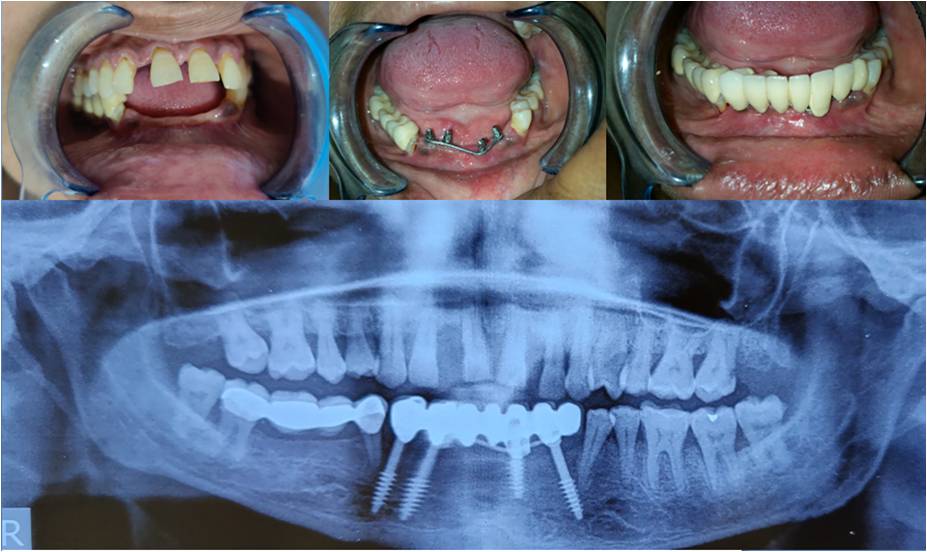

Dental Implants

We help you get a new set of teeth or a single tooth that matches your smile. Dental implants look, feel, and function like natural teeth, offering a lasting, comfortable solution.

Dentures

We offer dentures to restore smiles, enhancing oral function with replacements.